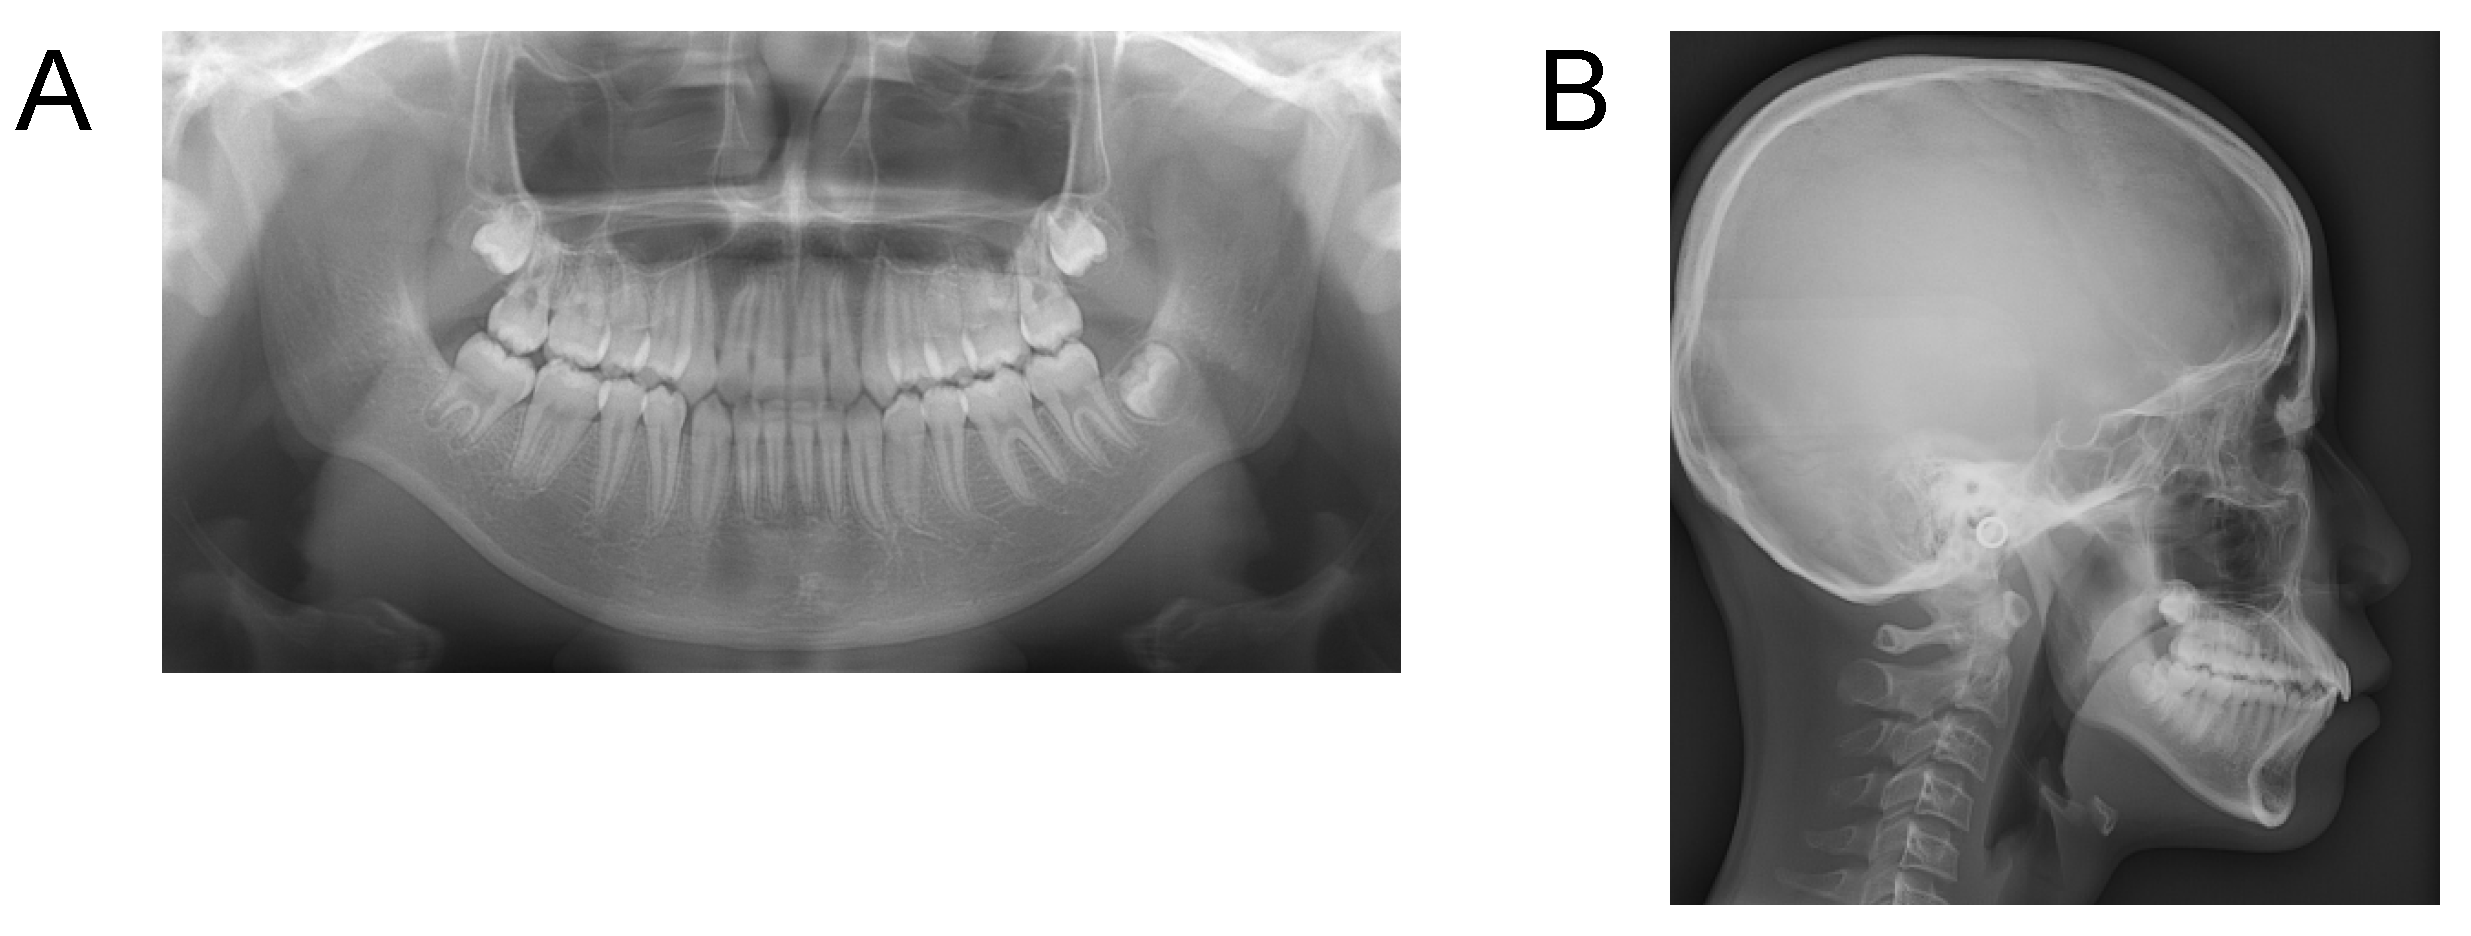

Case 1. Findings from initial examination